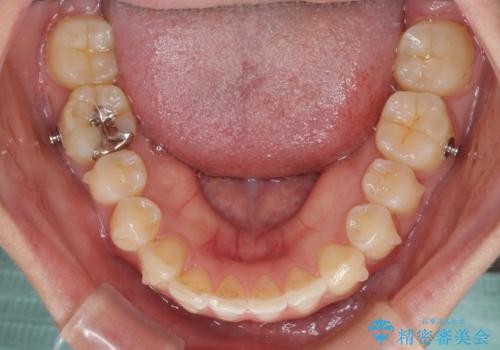

口元の突出感はインビザラインにより歯列を整え、その後に、前歯をオーダーメイドタイプのオールセラミッククラウンにて補綴治療することとしました。

長時間のマウスピース装着と、患者様自身でのゴムかけに協力いただき、口元の突出感をしっかりと改善することができました。

- マウスピース型矯正装置の長時間装着(1日20時間以上)が必須です